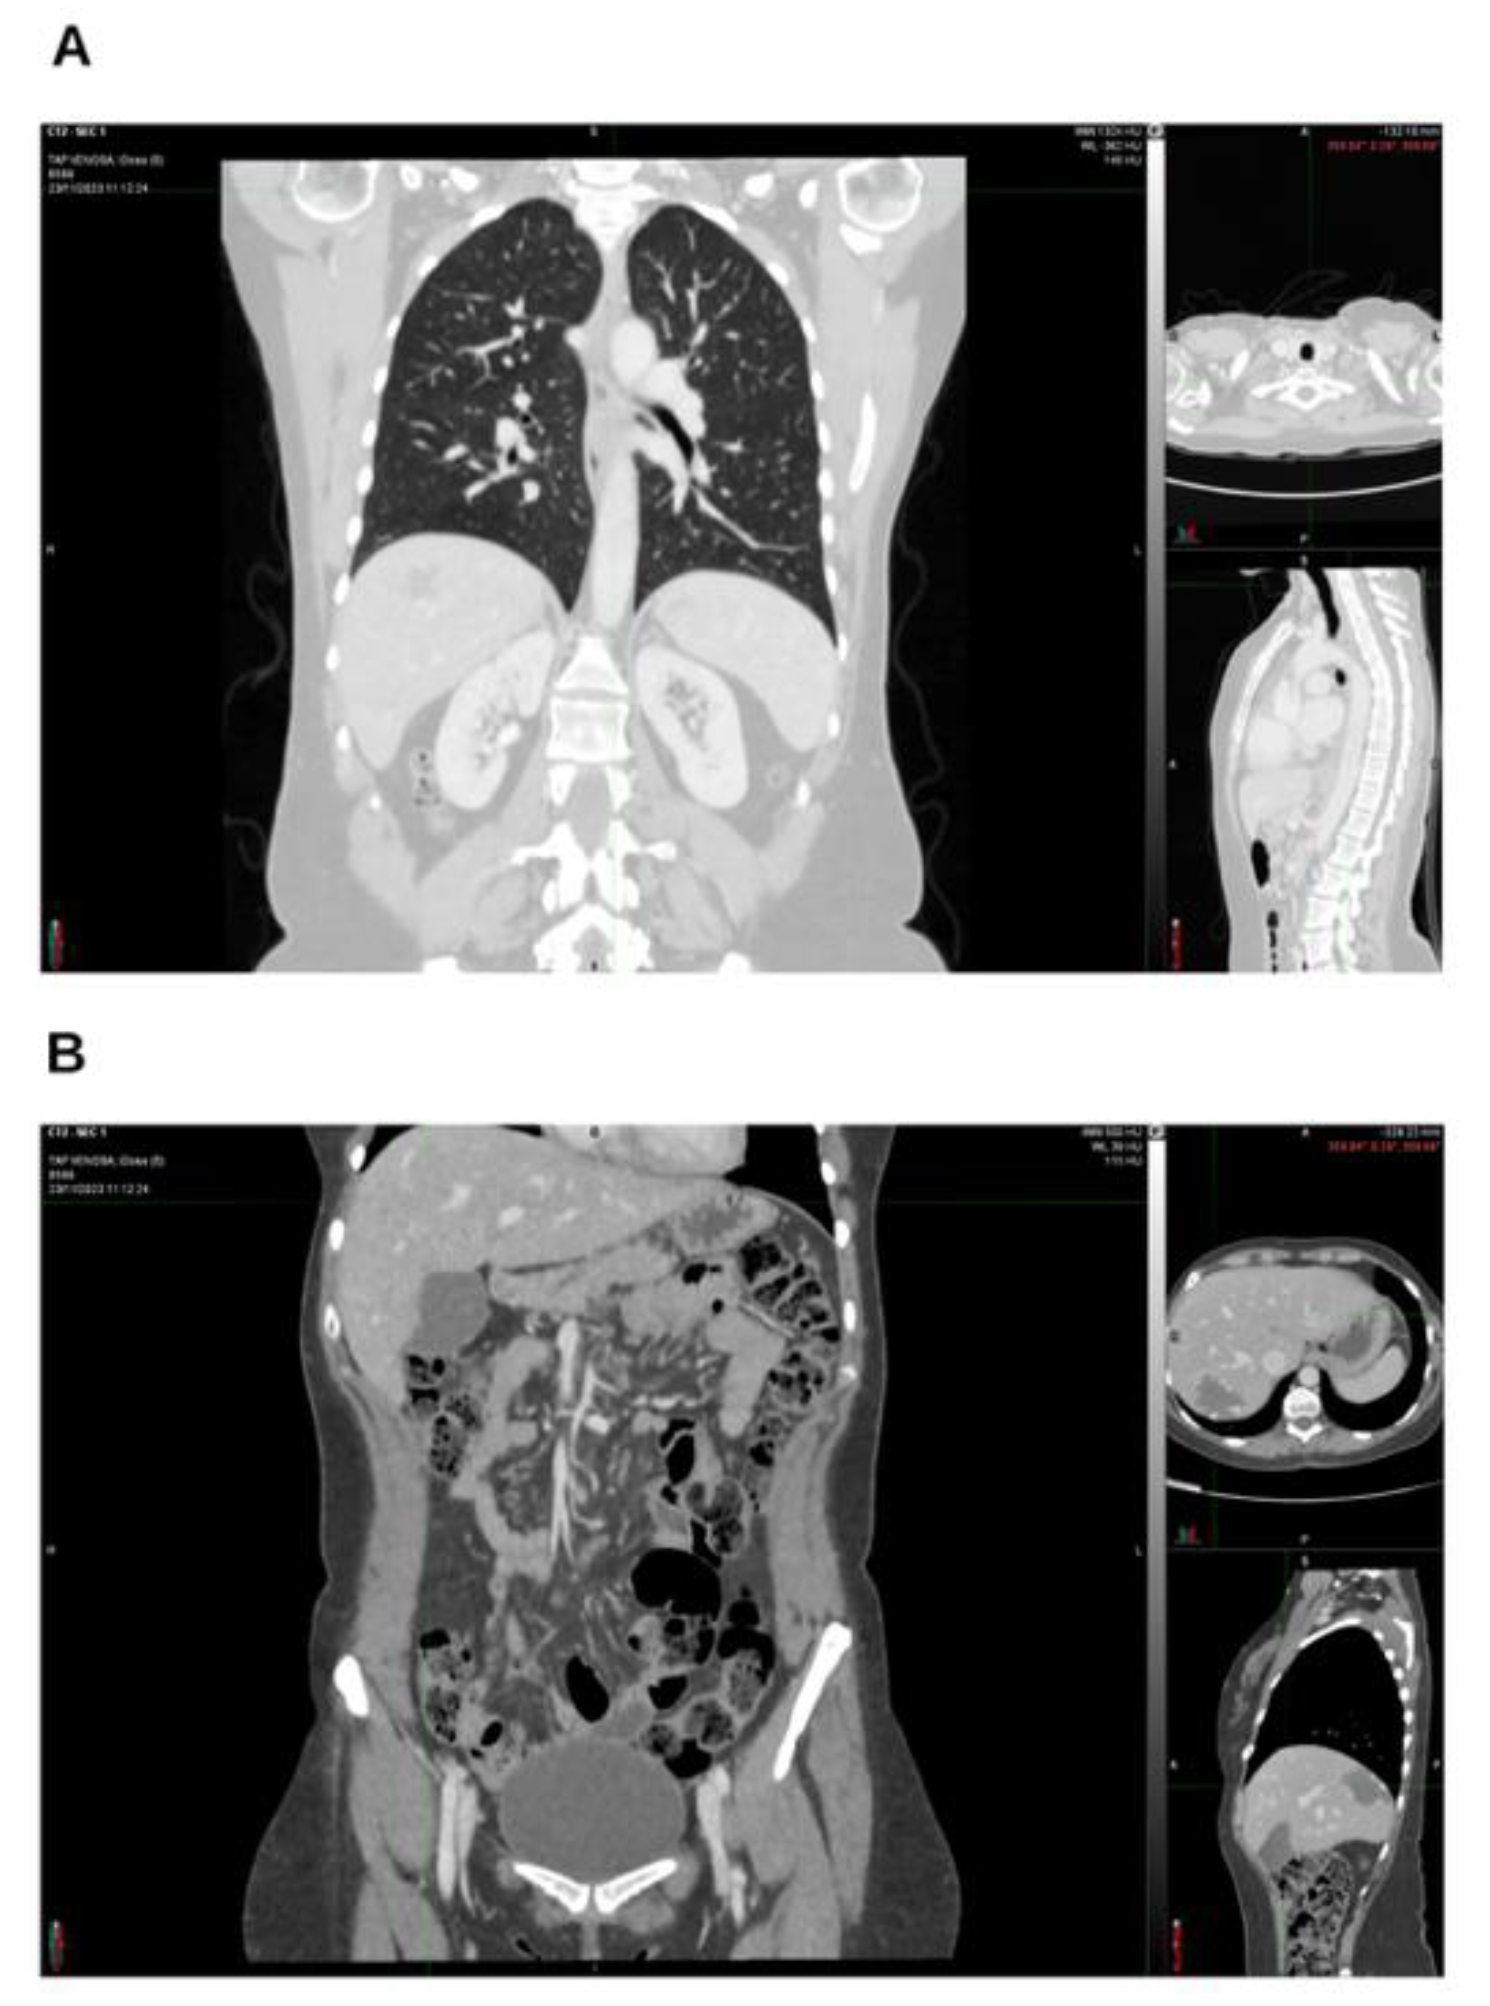

Background and Clinical Significance: Breast cancer is the most frequent malignancy in women. Advanced metastatic breast cancer is considered a treatable but incurable condition, with a median overall survival of only 2-3 years. Among its subtypes, triple-negative breast cancer (TNBC) accounts for a high proportion of breast cancer–related deaths. It is characterized by an aggressive clinical course, early recurrence, and a strong propensity for visceral and brain metastases. Case Presentation :We report the case of a Caucasian woman who, two years after being initially diagnosed and treated for TNBC, developed disease relapse with lung and mediastinal lymph node metastases. The patient received three months of chemotherapy combined with an adjuvant integrative protocol consisting of melatonin, cannabidiol, and oxygen–ozone therapy. This combined approach led to the complete disappearance of the lung nodules. Subsequently, stereotactic radiotherapy was performed and, in association with the ongoing integrative treatment, resulted in a significant reduction of mediastinal adenopathy. Introduction of immunotherapy, supported continuously by the same adjuvant strategy, achieved a complete and durable remission. Strikingly, the patient remained disease-free five years after the diagnosis of lung and mediastinal metastases. Conclusions: This clinical case highlights the potential benefit of using melatonin, cannabidiol, and oxygen–ozone therapy as part of an integrative approach in patients with aggressive metastatic TNBC. While it is not possible to establish causality from a single case, the sustained remission observed suggests that such unconventional adjuvant strategies could play a supportive role in enhancing the efficacy of standard oncologic therapies.